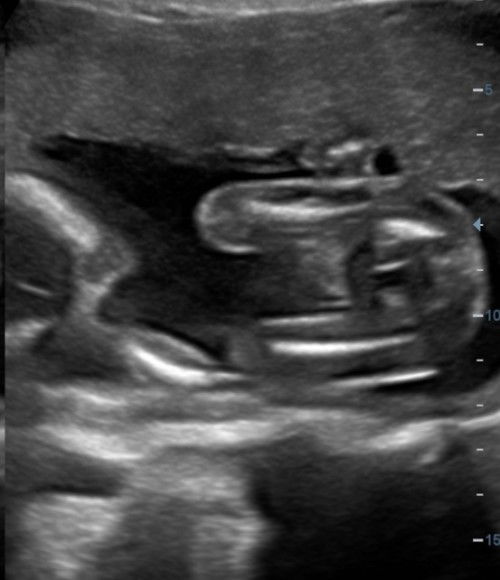

Hi, mommy semua, haritu pergi buat details scan. nak tanya kalau macamni girl ke boy? asalnya scan flat je (gambar1) doctor cakap girl dah nak habis scan tu saja scan gender lagi sekali keluar gini pulok (gambar 2) hihi doctor cakap nanti 26/27weeks boleh try scan gender lagi sekali 🥹🤭 #firstbaby #firstmom